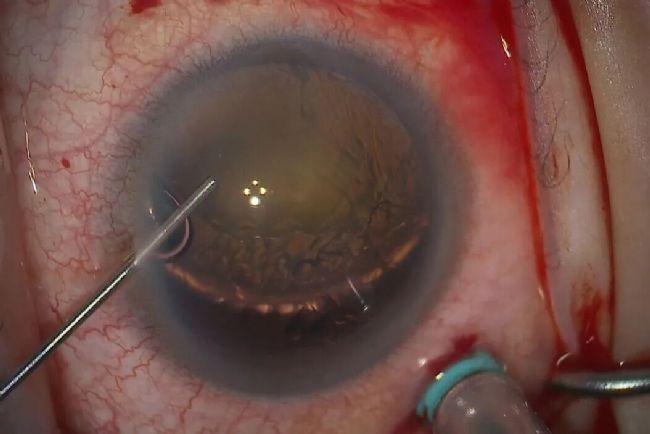

在白內(nèi)障手術(shù)中具有重要作用,使眼科醫(yī)生能夠觀察精細(xì)結(jié)構(gòu)并進(jìn)行精準(zhǔn)操作。尤其當(dāng)白內(nèi)障發(fā)生脫位時(shí),術(shù)者需準(zhǔn)確評(píng)估其位置并制定最安全有效的移除方案。

術(shù)中 OCT 等先進(jìn)技術(shù)為白內(nèi)障手術(shù)提供了額外的信息維度,可呈現(xiàn)前房結(jié)構(gòu)的替代視圖。該技術(shù)能顯示眼球表層下的解剖細(xì)節(jié),如前房玻璃體及晶狀體傾斜度等。

手術(shù)目標(biāo)是通過(guò)處理脫位性白內(nèi)障,實(shí)現(xiàn)長(zhǎng)期良好效果,避免未來(lái)發(fā)生晶狀體再脫位。